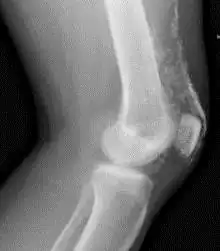

![]() Rayos X de la rodilla de un paciente con dermatomiositis | ||